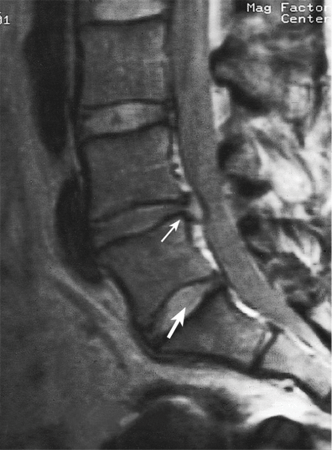

Figure 6: MRI view of herniated discs.

Often, a part of a vertebral body, the lamina, is also removed for surgical access and this procedure is known as a laminectomy. The problem with surgery around spinal nerve roots is that manipulation of tissues often leads to scarring that then again pressures the nerve root. This is particularly likely when a person has had multiple back surgeries. Many claimants who complain of chronic back pain and have a history of back surgery near nerve roots have scarring that can be identified on CT or MRI scans. In the absence of trauma, most HNPs occur in the lumbar (lower) spine, especially at the level of L5-S1.